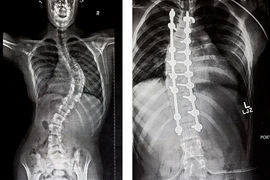

(khoahocdoisong.vn) - Lần đầu tiên Bệnh viện Đa khoa Phú Thọ đã phẫu thuật thành công chỉnh hình cột sống cho trẻ bị vẹo cột sống nặng > 45 độ. Đây là một kĩ thuật phức tạp, thường được triển khai ở bệnh viện tuyến trung ương. Phẫu thuật sớm không chỉ giúp trẻ lấy lại vóc dáng mà còn tránh các biến chứng nguy hiểm về chức năng hô hấp, tim mạch...

(khoahocdoisong.vn) - Biến dạng cột sống rất nặng và cứng nên bắt buộc phải phẫu thuật 2 đường. Phẫu thuật giúp chỉnh cong vẹo, trẻ cao thêm được 11-13cm. Hãy nhận biết các dấu hiệu trẻ bị biến dạng cột sống để cho trẻ đi khám sớm.